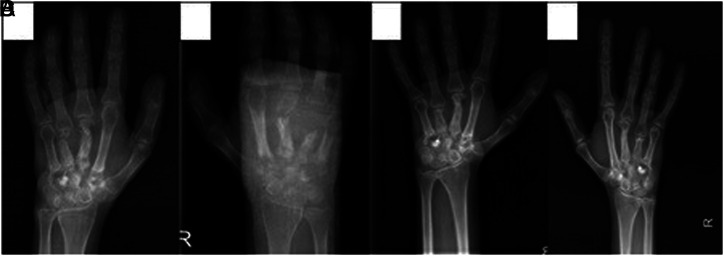

Osteomyelitis with a Pathologic Fracture, Mortal Liver Abscess, and Cholelithiasis: Distinct Features in two Families with the Same p47-phox Mutation.